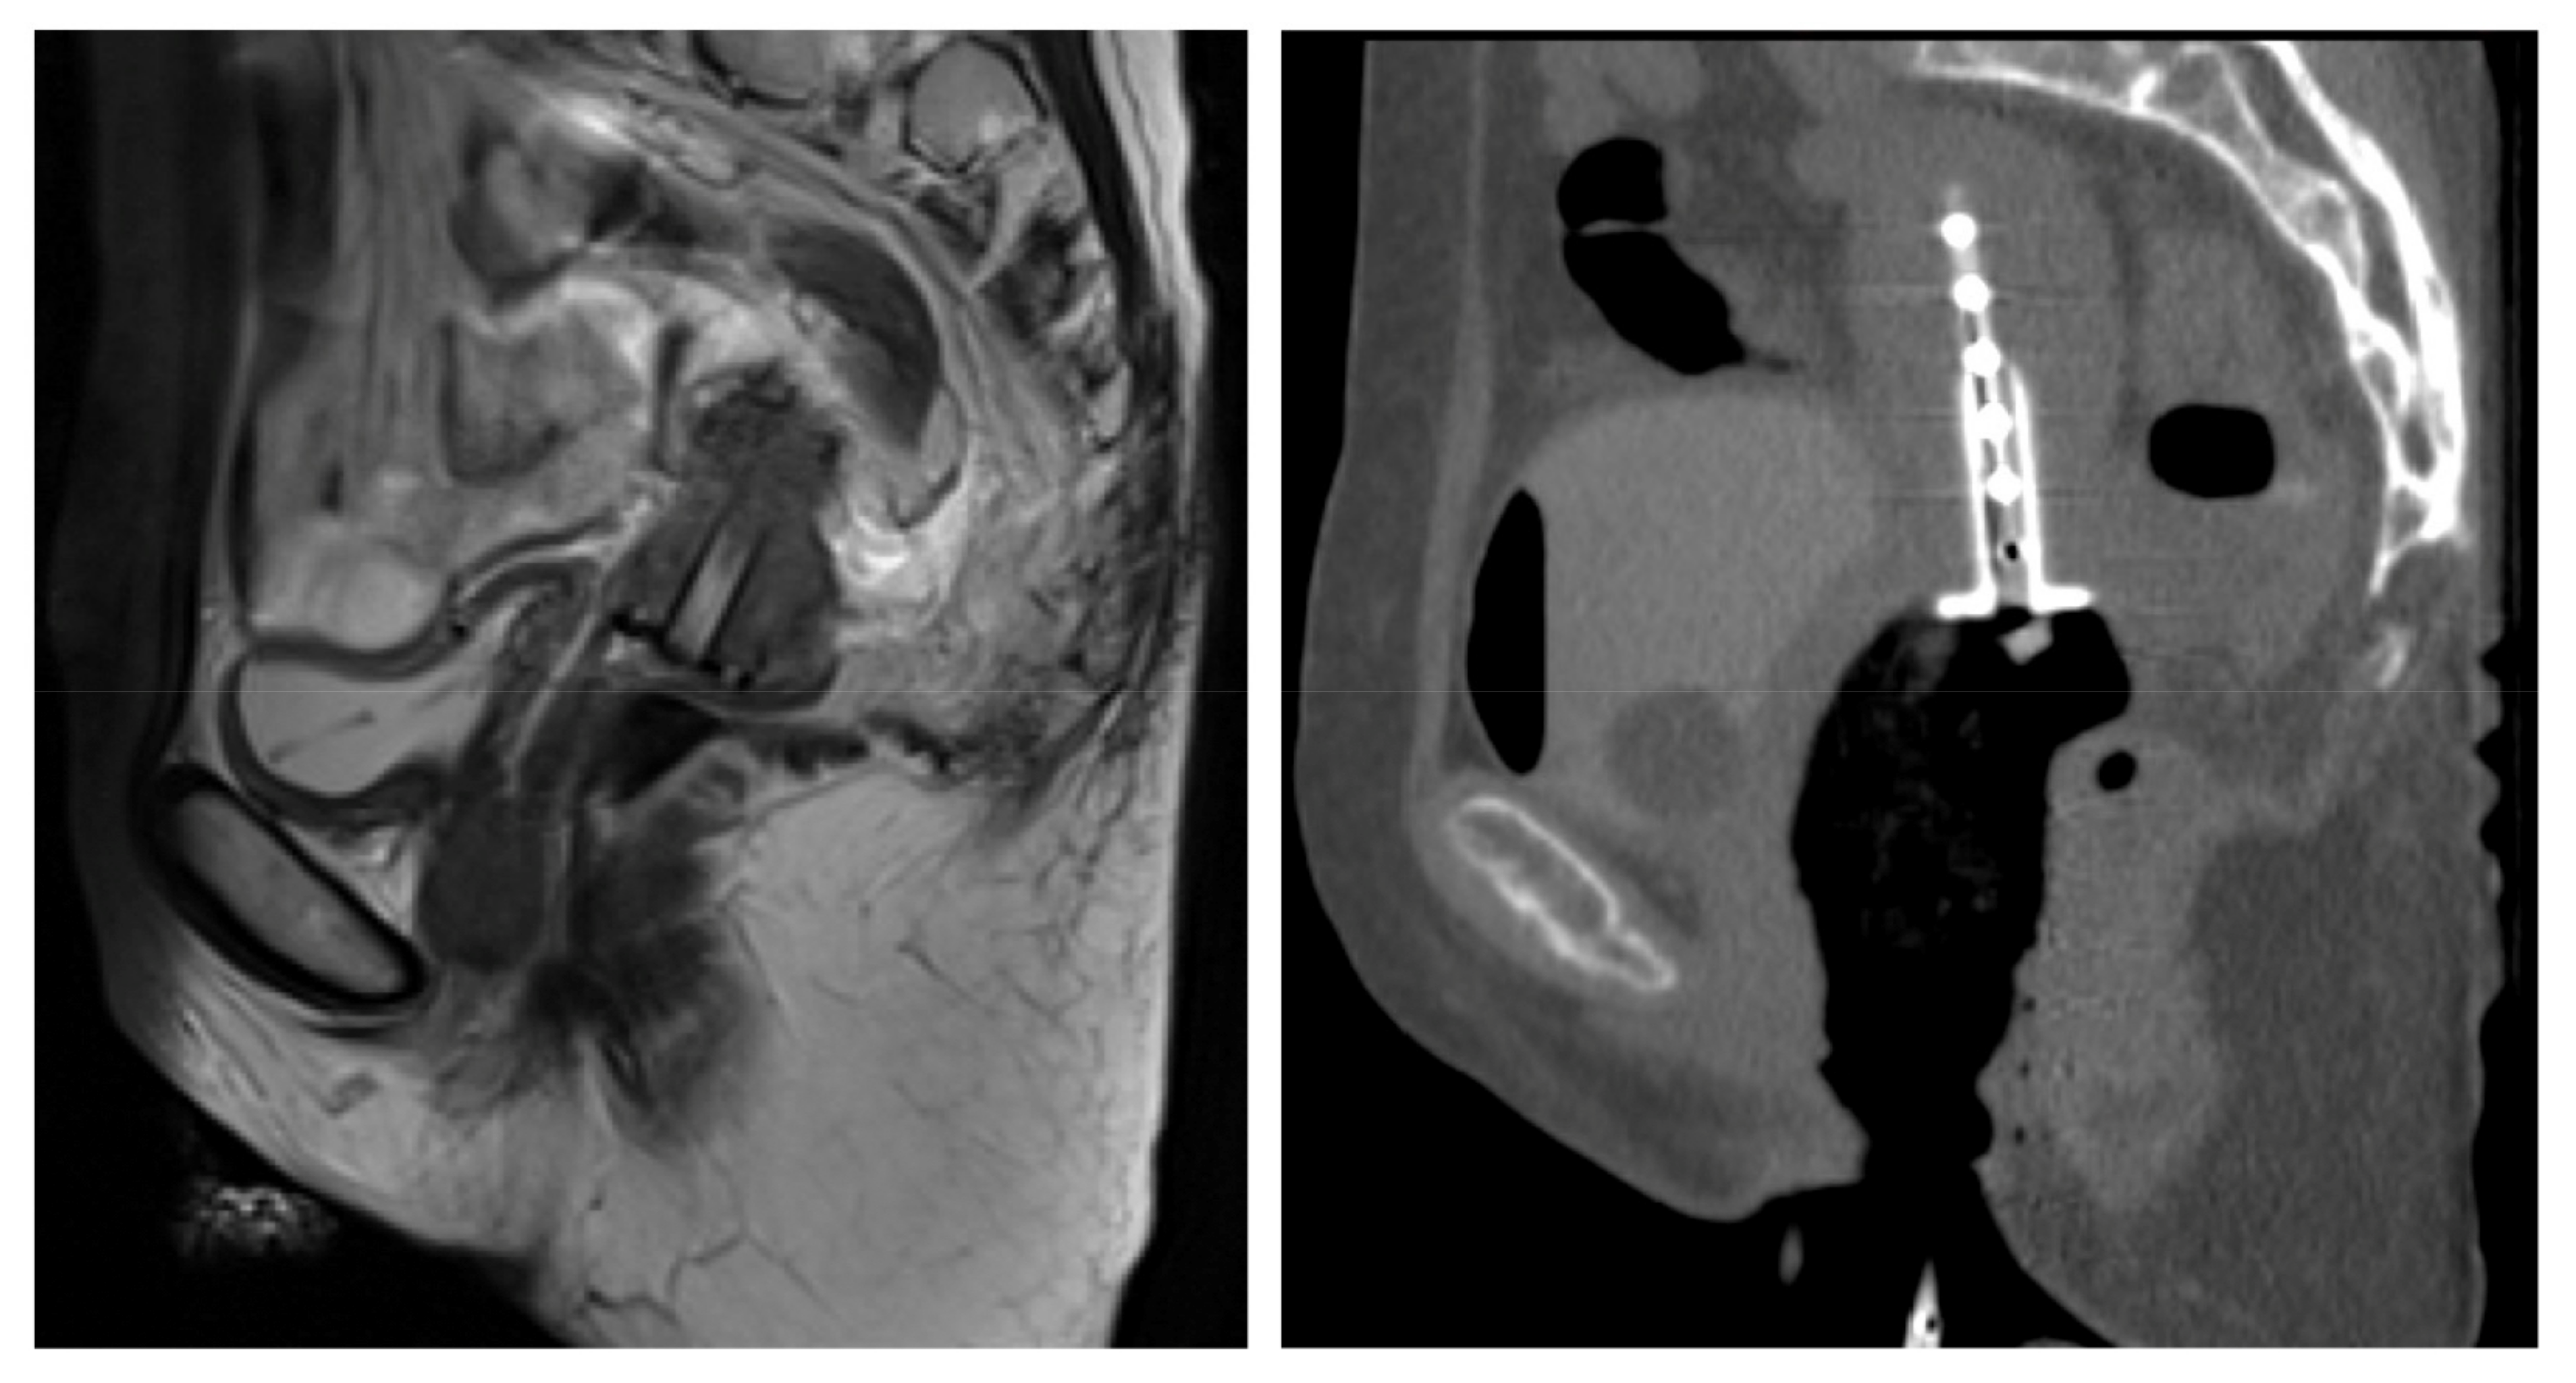

The Fusion of MRI and CT in the Planning of Brachytherapy for Cancer of the Uterine Cervix

2. Materials and Methods